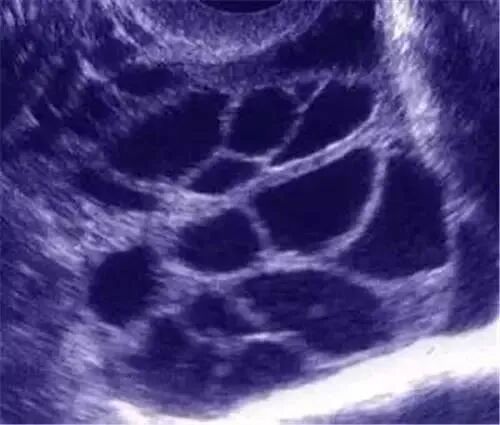

卵巢过度刺激综合征(OHSS)为体外受孕辅助生育的主要并发症之一,是一种人体对促排卵药物产生的过度反应,以双侧卵巢多个卵泡发育、卵巢增大、毛细血管通透性异常、异常体液和蛋白外渗进入人体第三间隙为特征而引起的一系列临床症状的并发症。

OHSS主要临床表现为卵巢囊性增大、毛细血管通透性增加、体液积聚于组织间隙,引起腹腔积液、胸腔积液,伴局部或全身水肿。

(图:B超示卵巢过度刺激声像)